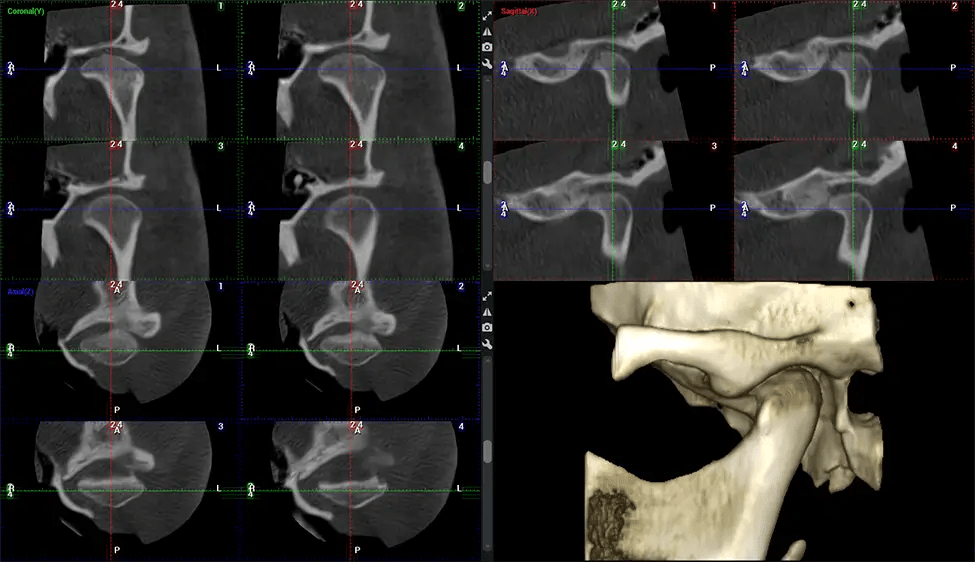

Después del proceso de escaneo, las imágenes de rayos X capturadas son procesadas por el software CBCT, que aplica algoritmos para reconstruir una imagen 3D detallada del área escaneada. El software recopila estas imágenes de rayos X individuales y crea una representación digital en 3D de la anatomía del paciente. El dentista o el radiólogo pueden ver y analizar la imagen CBCT 3D reconstruida. Esta imagen se puede manipular, rotar y acercar o alejar para examinar estructuras específicas y evaluar la condición del paciente.

Planmeca Viso G7 CBCT (Cone Beam CT Scan) está diseñado para superar las demandas de los líderes de la industria, los especialistas y las grandes instituciones. Tiene un gran sensor de ø25×30 cm con cuatro cámaras integradas. Puede capturar tamaños de volumen ilimitados, desde ø3×3 cm hasta ø30x30cm, capturando el casquete escutelario a través de C7 en la columna cervical. Planmeca Viso G7 ofrece el escaneo de volumen único más grande de la industria de ø30×19 cm. Está preparado para manejar modalidades de imágenes avanzadas como la tecnología Planmeca ProFace® y Planmeca 4D™ Jaw Motion. El soporte occipital para la cabeza permite una visión sin obstáculos del tejido facial.